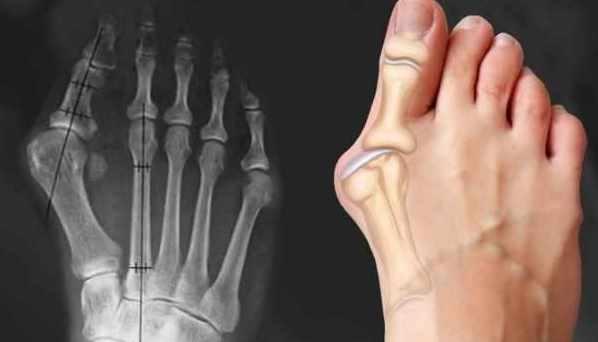

Массаж при вальгусной деформации стопы (Александр Иванов)

Тема в разделе "Массаж"